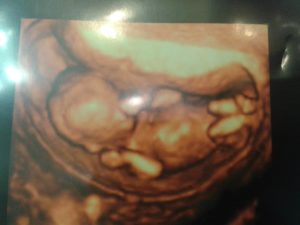

image https://pixabay.com/photos/pregnant-baby-echo-ultrasound-518793/